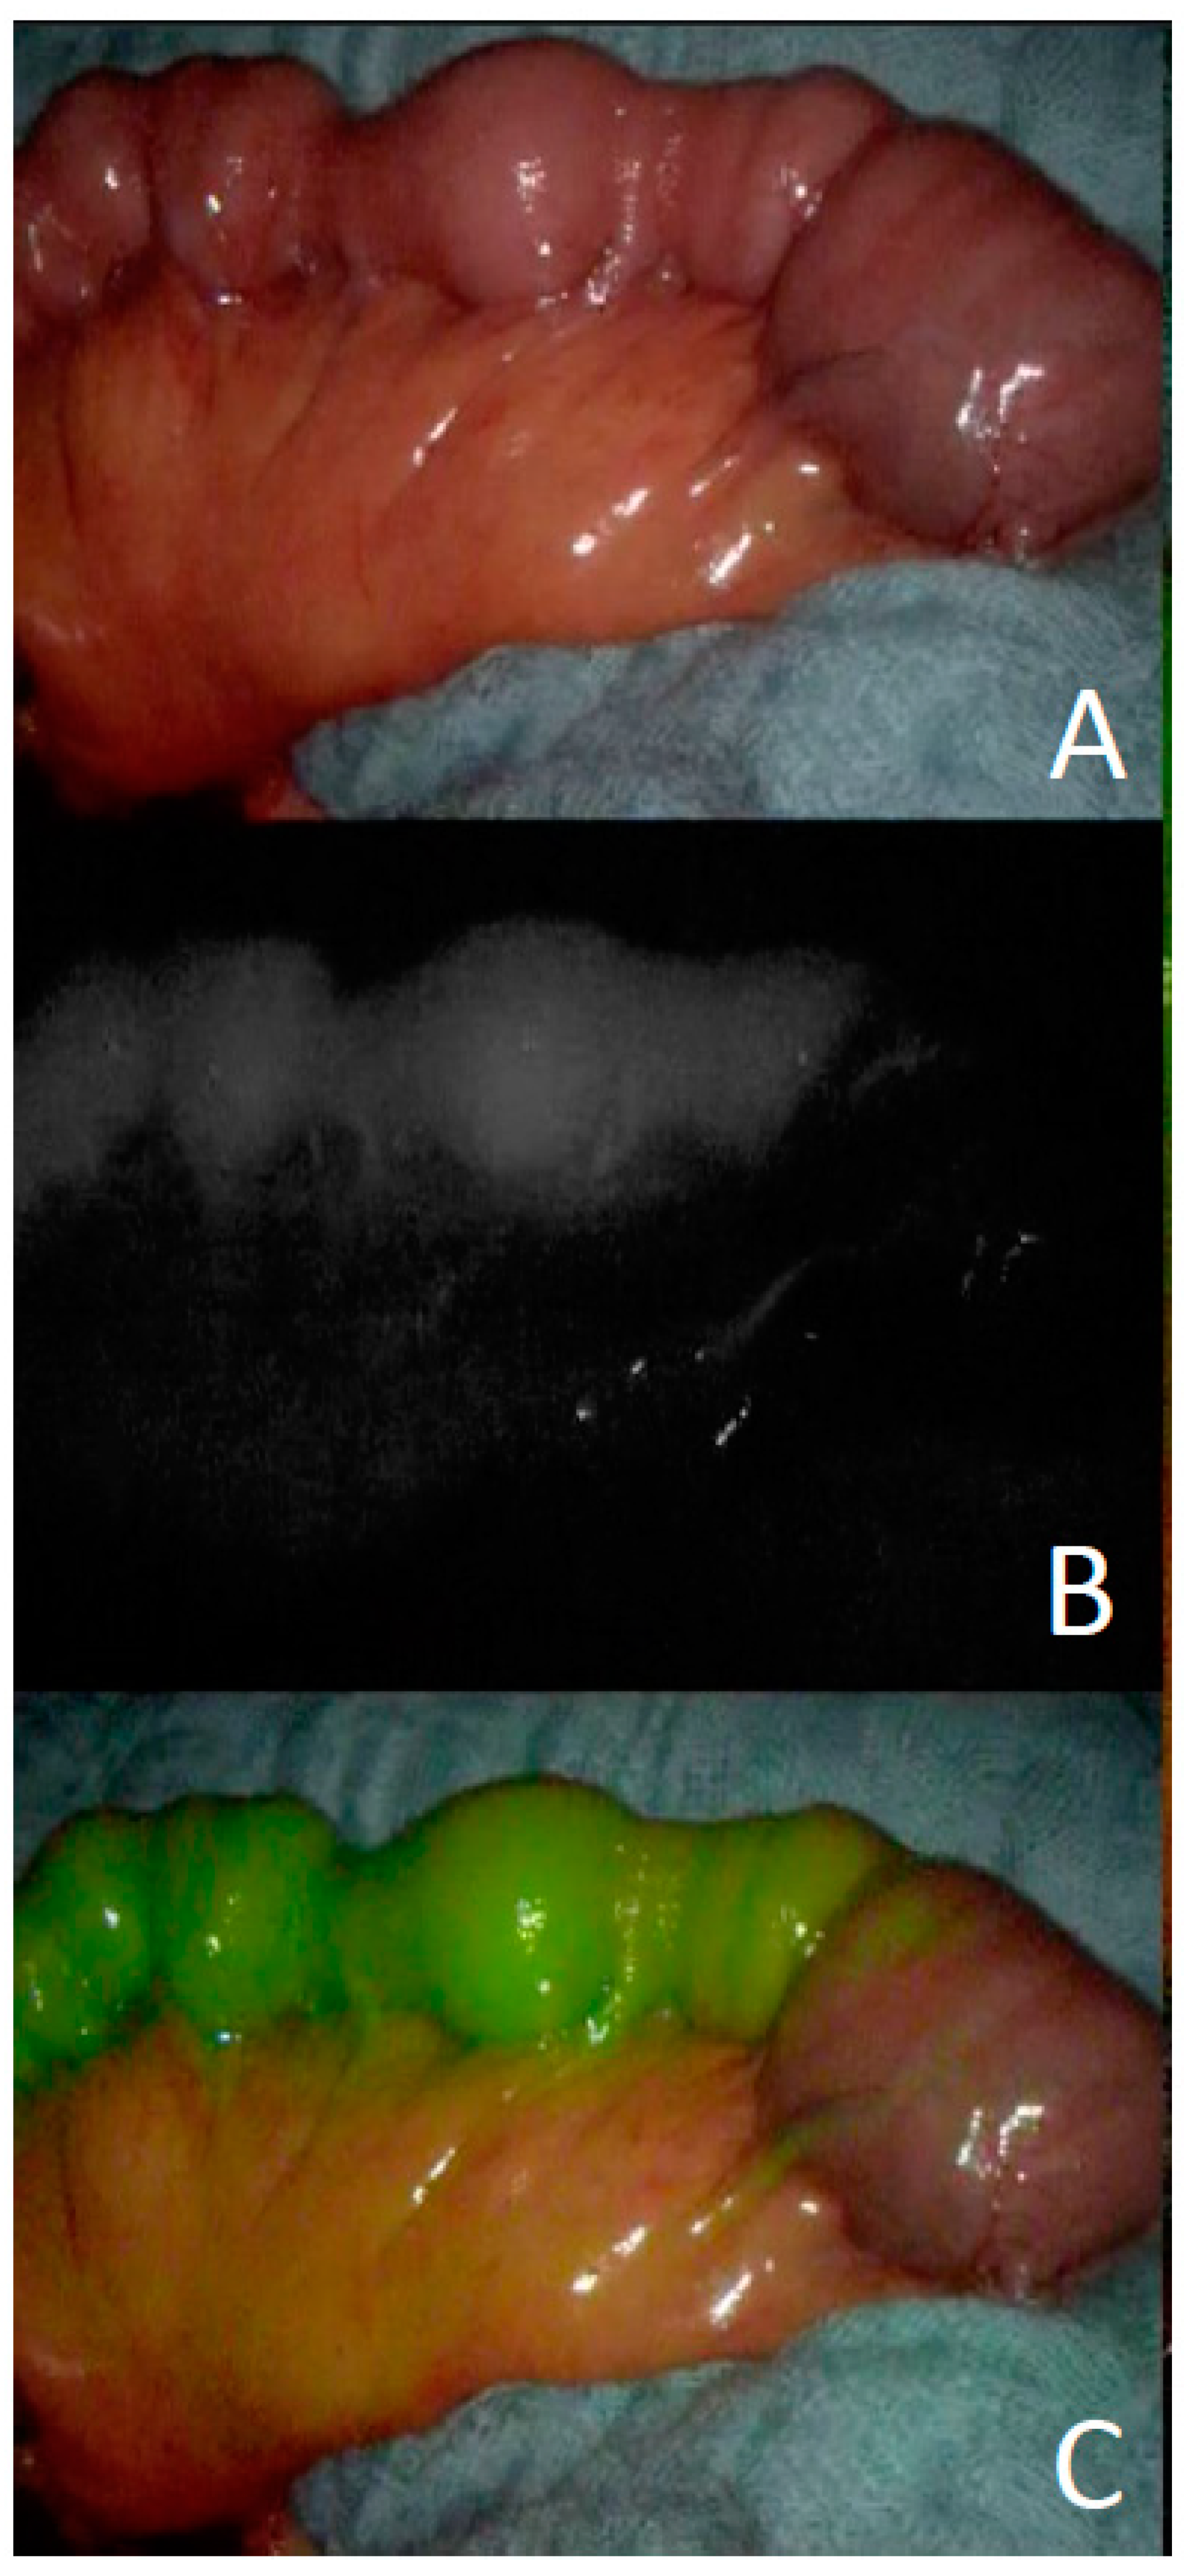

2.6. Intraoperative Perfusion Control of Flaps

- Karampinis, I.; Ronellenfitsch, U.; Mertens, C.; Gerken, A.; Hetjens, S.; Post, S.; Kienle, P.; Nowak, K. Indocyanine green tissue angiography affects anastomotic leakage after esophagectomy. A retrospective, case-control study. Int. J. Surg. 2017, 48, 210–214. [Google Scholar] [CrossRef] [PubMed]

- Nowak, K.; Karampinis, I.; Gerken, A.L.H. Application of Fluorescent Dyes in Visceral Surgery: State of the Art and Future Per-spectives. Visc. Med. 2020, 36, 80–87. [Google Scholar] [CrossRef]

- Bigdeli, A.K.; Thomas, B.; Falkner, F.; Gazyakan, E.; Hirche, C.; Kneser, U. The Impact of Indocyanine-Green Fluorescence Angi-ography on Intraoperative Decision-Making and Postoperative Outcome in Free Flap Surgery. J. Reconstr. Microsurg. 2020, 36, 556–566. [Google Scholar] [PubMed]